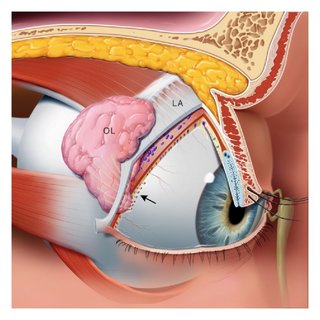

Ο ρόλος του ύψους της φιάλης στο χειρουργείο της φακοθρυψίας

Ο επιστημονικός συνεργάτης του Ελληνικού Κολλεγίου Οφθαλμολογίας, κύριος Σίσκος Γεώργιος MD, Msc, FEBO μας παρουσιάζει στο πρώτο βίντεο της εκπαιδευτικής ενότητας: “Θεωρία και τεχνικές φακοθρυψίας”, το ρόλο του ύψους της φιάλης πλύσης κατά την εκτέλεση των διαφόρων βημάτων στο χειρουργείο του καταρράκτη.